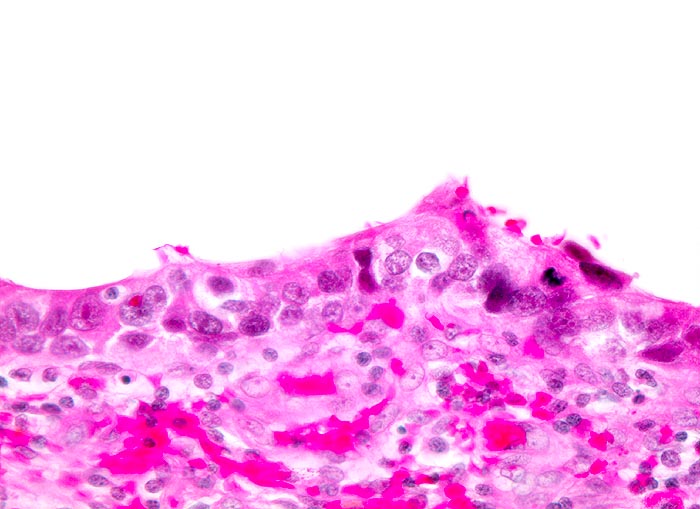

PathoPic – image database / PathoPic ID 3629 - Carcinoma in situ des Urothels

Carcinoma in situ des Urothels

Verschmälertes Urothel. Deutlich ausgeprägte Zellkernpolymorphie. Starke Vergösserung der hyperchromatischen Kerne mit Verschiebung der Kern-Zytoplasmarelation.

Invasives Plattenepithelkarzinom der Harnblase.

320